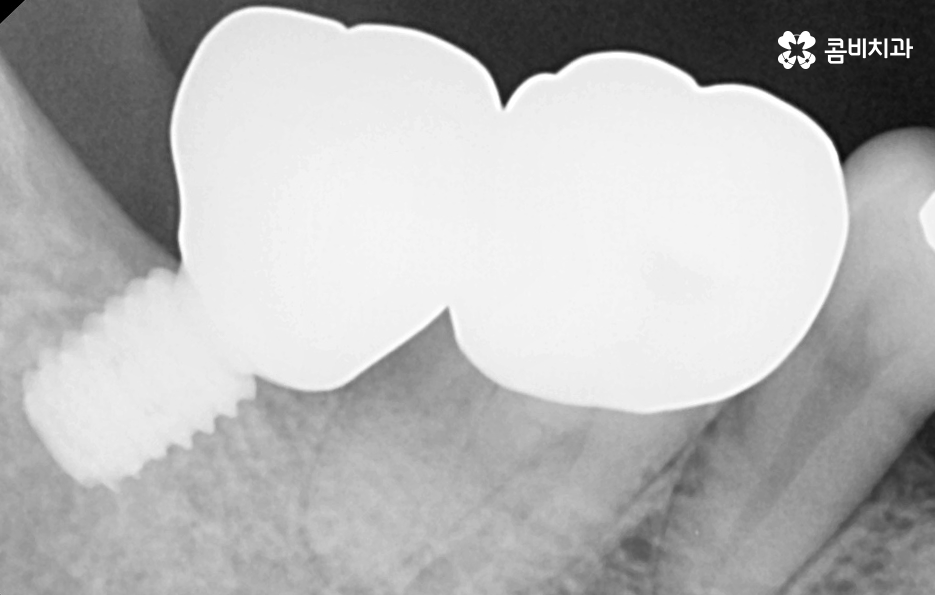

우리가 보편적으로 생각하게 되는 임플란트 치료기간의 경우 치아 하나를 상실하고 임플란트를 1:1로 치료할 때 예상 기간에 대해서 고려하게 되는 경우가 기본적인 접근 방법이라면 실질적으로 치과에서 임플란트를 하게 되는 연령대를 보더라도 보통 50대에서 60대 이후에 치아를 상실하게 되는 환자분들이 급증하기 때문에 위 사진의 사례처럼 여러 치아를 상실하고 임플란트를 식립하게 되는 경우도 많을 거예요